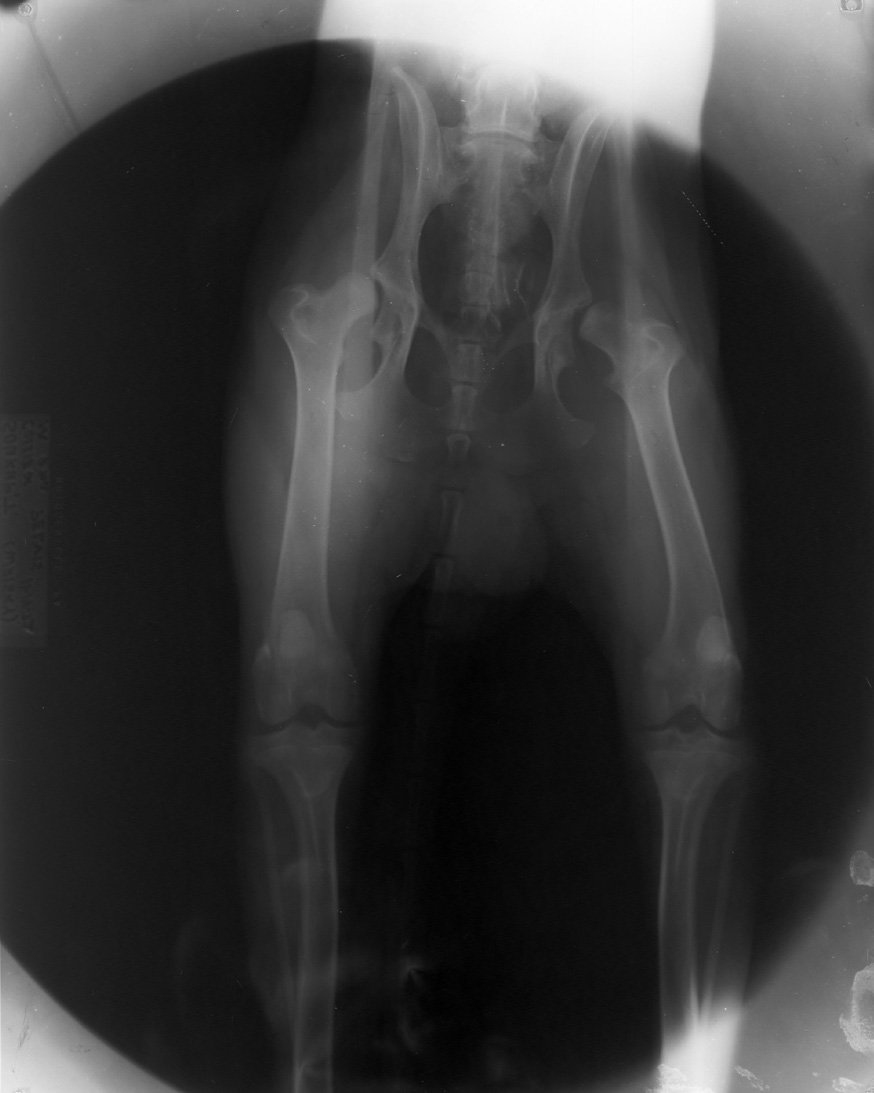

White spots due to dirty screens. Note circular border of radiation - old style x-ray units used cones before collimators were invented.